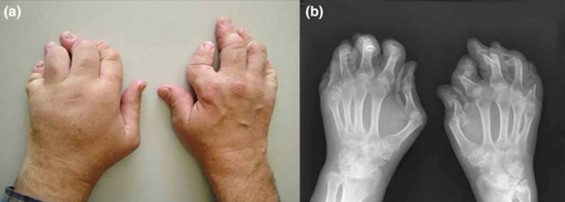

Left: PsA affecting hands, causing severely damaged and deformed joints; Right: XRay of affected hands.

Photos retrieved from Health Jade.